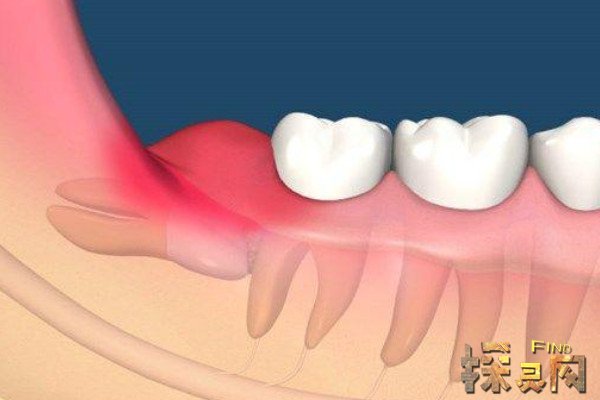

人在成年之后一般都会长智齿,在其生长期间可能会出现牙龈肿痛的情况,严重影响人们的日常生活,所以很多医生都建议将其拔掉,但总有人会因为拔掉后出现的不良反应而后悔。事实上,智齿对人的危害没有那么大,如果其生长状态比较良好,则没有强行拔除的必要,除非是畸形智齿。